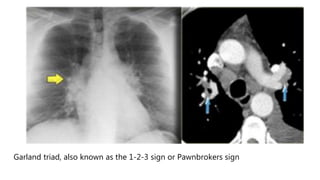

Garland triad, also known as the 1-2-3 sign or Pawnbrokers sign

Garland triad, alsoknown as the 1-2-3 sign or Pawnbrokers sign

 Lymphadenopathy in left hilus, right hilus and paratracheal. Often

with calcifications.

 Common findings: Small nodules in a perilymphatic distribution (i.e. along subpleural surface and fissures, along interlobular septa and the peribronchovascular bundle).  Upper and middle zone predominance.  Lymphadenopathy in left hilus, right hilus and paratracheal. Often with calcifications.